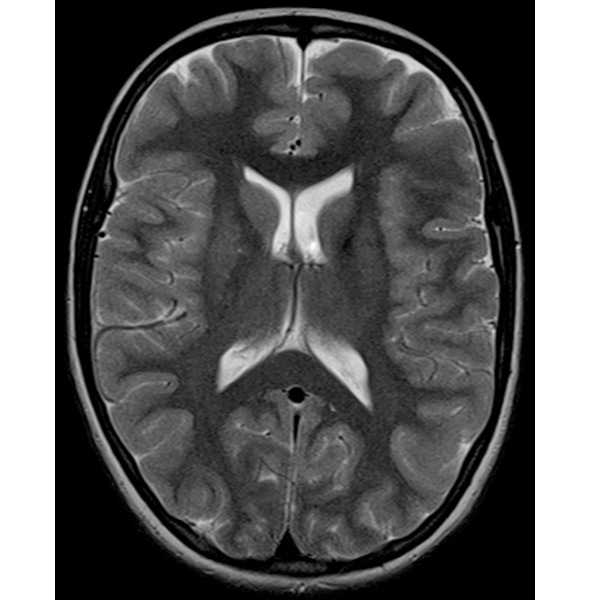

Помимо всего этого, у мозга есть еще одна потрясающая способность – способность сжиматься без какой-либо травмы вещества мозга, если в голове постепенно уменьшается полезный объем. На фото вы видите МРТ человека с нормотензивной гидроцефалией (стр.7), а рядом обычное МРТ (стр.6).

При нормотензивной гидроцефалии объем желудочков мозга увеличивается постепенно. Вы видите, насколько мало места в черепе осталось непосредственно для головного мозга, примерно в два раза меньше нормального объема. И вот этот человек с такими проблемами в голове ходил на работу, начал отмечать замедленность мышления, снижения скорости обработки информации, поэтому обратился к неврологу. Нейрохирурги выполнили ему операцию, после которой желудочки мозга стали нормального размера. И он вновь стал думать так же быстро и великолепно запоминать информацию. И за несколько месяцев сжатия в его мозге не погибли клетки, там не возникло участков некроза, видимых на МРТ. Представьте, если бы мы сдавили мышцы бедра или предплечья. Уже через несколько часов был бы некроз мышц, а здесь несколько месяцев – и без последствий. Таким образом, компенсаторная способность к уменьшению объема у мозга совершенно поражает воображение.